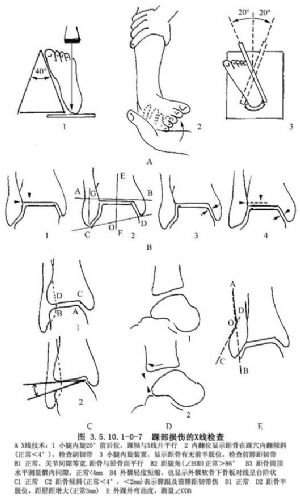

踝部骨折的診斷主要依據X線攝片。球管須對準踝關節中心,前後位投照小腿在內旋15°~25°位,使經踝軸線與X線底片平行。

如可疑距骨前結節損傷,則在小腿外旋45°位做前後及側位投照,顯示韌帶損傷。單純前腓距韌帶傷在前後位片上不出現距骨內翻,但腓距關節間隙增寬。只有外側副韌帶完全斷裂,距骨才傾倒內翻。

側副韌帶的隱性缺陷,在側位片上可見到距骨向前移位(圖3.5.10.1-0-7)。